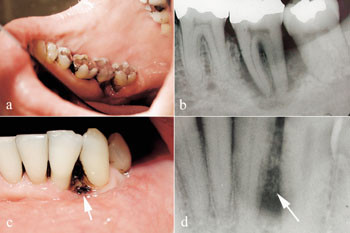

HIV-infeksjon er forbundet med høyere forekomst av spesielle former for gingivale og periodontale sykdommer som sjelden opptrer hos systemisk friske personer: lineært gingivalt erytem, nekrotiserende ulcerøs gingivitt og periodontitt (1 – 4). Nekrotiserende periodontale sykdommer (fig 1) er funnet å være assosiert med graden av pasientens immunsvikt – prevalensen i asymptomatiske HIV-positive pasienter er lav (< 0,5 %), men kan stige opp mot 10 % med progrediering av HIV-infeksjonen (5 – 7).

Pasienten. En 38 år gammel mann ble i april 1999 henvist til Avdeling for periodonti ved Det odontologiske fakultet i Oslo fra sin private tannlege på grunn av nekrotiske og ulcerøse periodontale lesjoner (fig 1). Den kliniske undersøkelsen avdekket foruten nekrotiske periodontale lesjoner også at pasienten hadde oral candidiasis (pseudomembranøs type). Munnhygienen var god, det var ikke synlig dentalt plakk. I den videre anamnesen fortalte han at han i 1995 hadde hatt et utbrudd med herpes zoster, og at han var til behandling ved Aker sykehus for idiopatisk trombocytopenisk purpura på henvisningstidspunktet. Denne diagnosen hadde han hatt siden januar 1998 og ble for dette medisinert med immunsuppressive medikamenter (Prednisolon og Imurel). Han hadde gjennomgått en splenektomi, da trombocytopenien ikke bedret seg til tross for medisineringen.

Pasienten hadde et meget lavt antall CD4-positive T-lymfocytter i perifert blod da han ble henvist til Avdeling for periodonti med nekrotisk periodontitt og oral candidose. Dette er sammenfallende med tidligere rapporter, hvor lavt antall CD4-positive T-lymfocytter er assosiert med alvorlighetsgrad og progrediering av periodontitt (3 – 5, 9, 11). Klinisk hadde vår pasient et horisontalt festetap uten dype beinlommer (fig 1), noe som stemmer overens med nekrotisk periodontitt (2).

Vi har i våre studier funnet at HIV-positive pasienter med kronisk marginal periodontitt har et inflammatorisk celleinfiltrat i inflammert gingiva som ikke bare er fokusert mot periodontallommens bunn, men også mot oralt epitel (16 – 20). Det var også en signifikant økning i antall makrofager, mastceller, nøytrofile granulocytter og plasmaceller hos HIV-positive med periodontitt sammenliknet med HIV-negative pasienter (16 – 20). Den store økningen i antall leukocytter og den uvanlige lokaliseringen var uavhengig av stadium i HIV-infeksjonen. Det er mulig at en slik utbredelse av celleinfiltratet kan predisponere for nekrotisk periodontitt hos denne pasientgruppen. En massiv frigjøring av potente vevsdestruktive mediatorer kan forårsake det horisontale festetapet som ofte sees hos HIV-positive pasienter (fig 1) (16 – 20). Det siste kan tenkes skje ved bortfall av funksjonelle CD4-positive T-lymfocytter, som er viktige regulatorceller i immunforsvaret, og kan forklare den observerte korrelasjonen mellom lavt antall CD4-positive T-lymfocytter og nekrotisk periodontitt hos denne pasientgruppen.